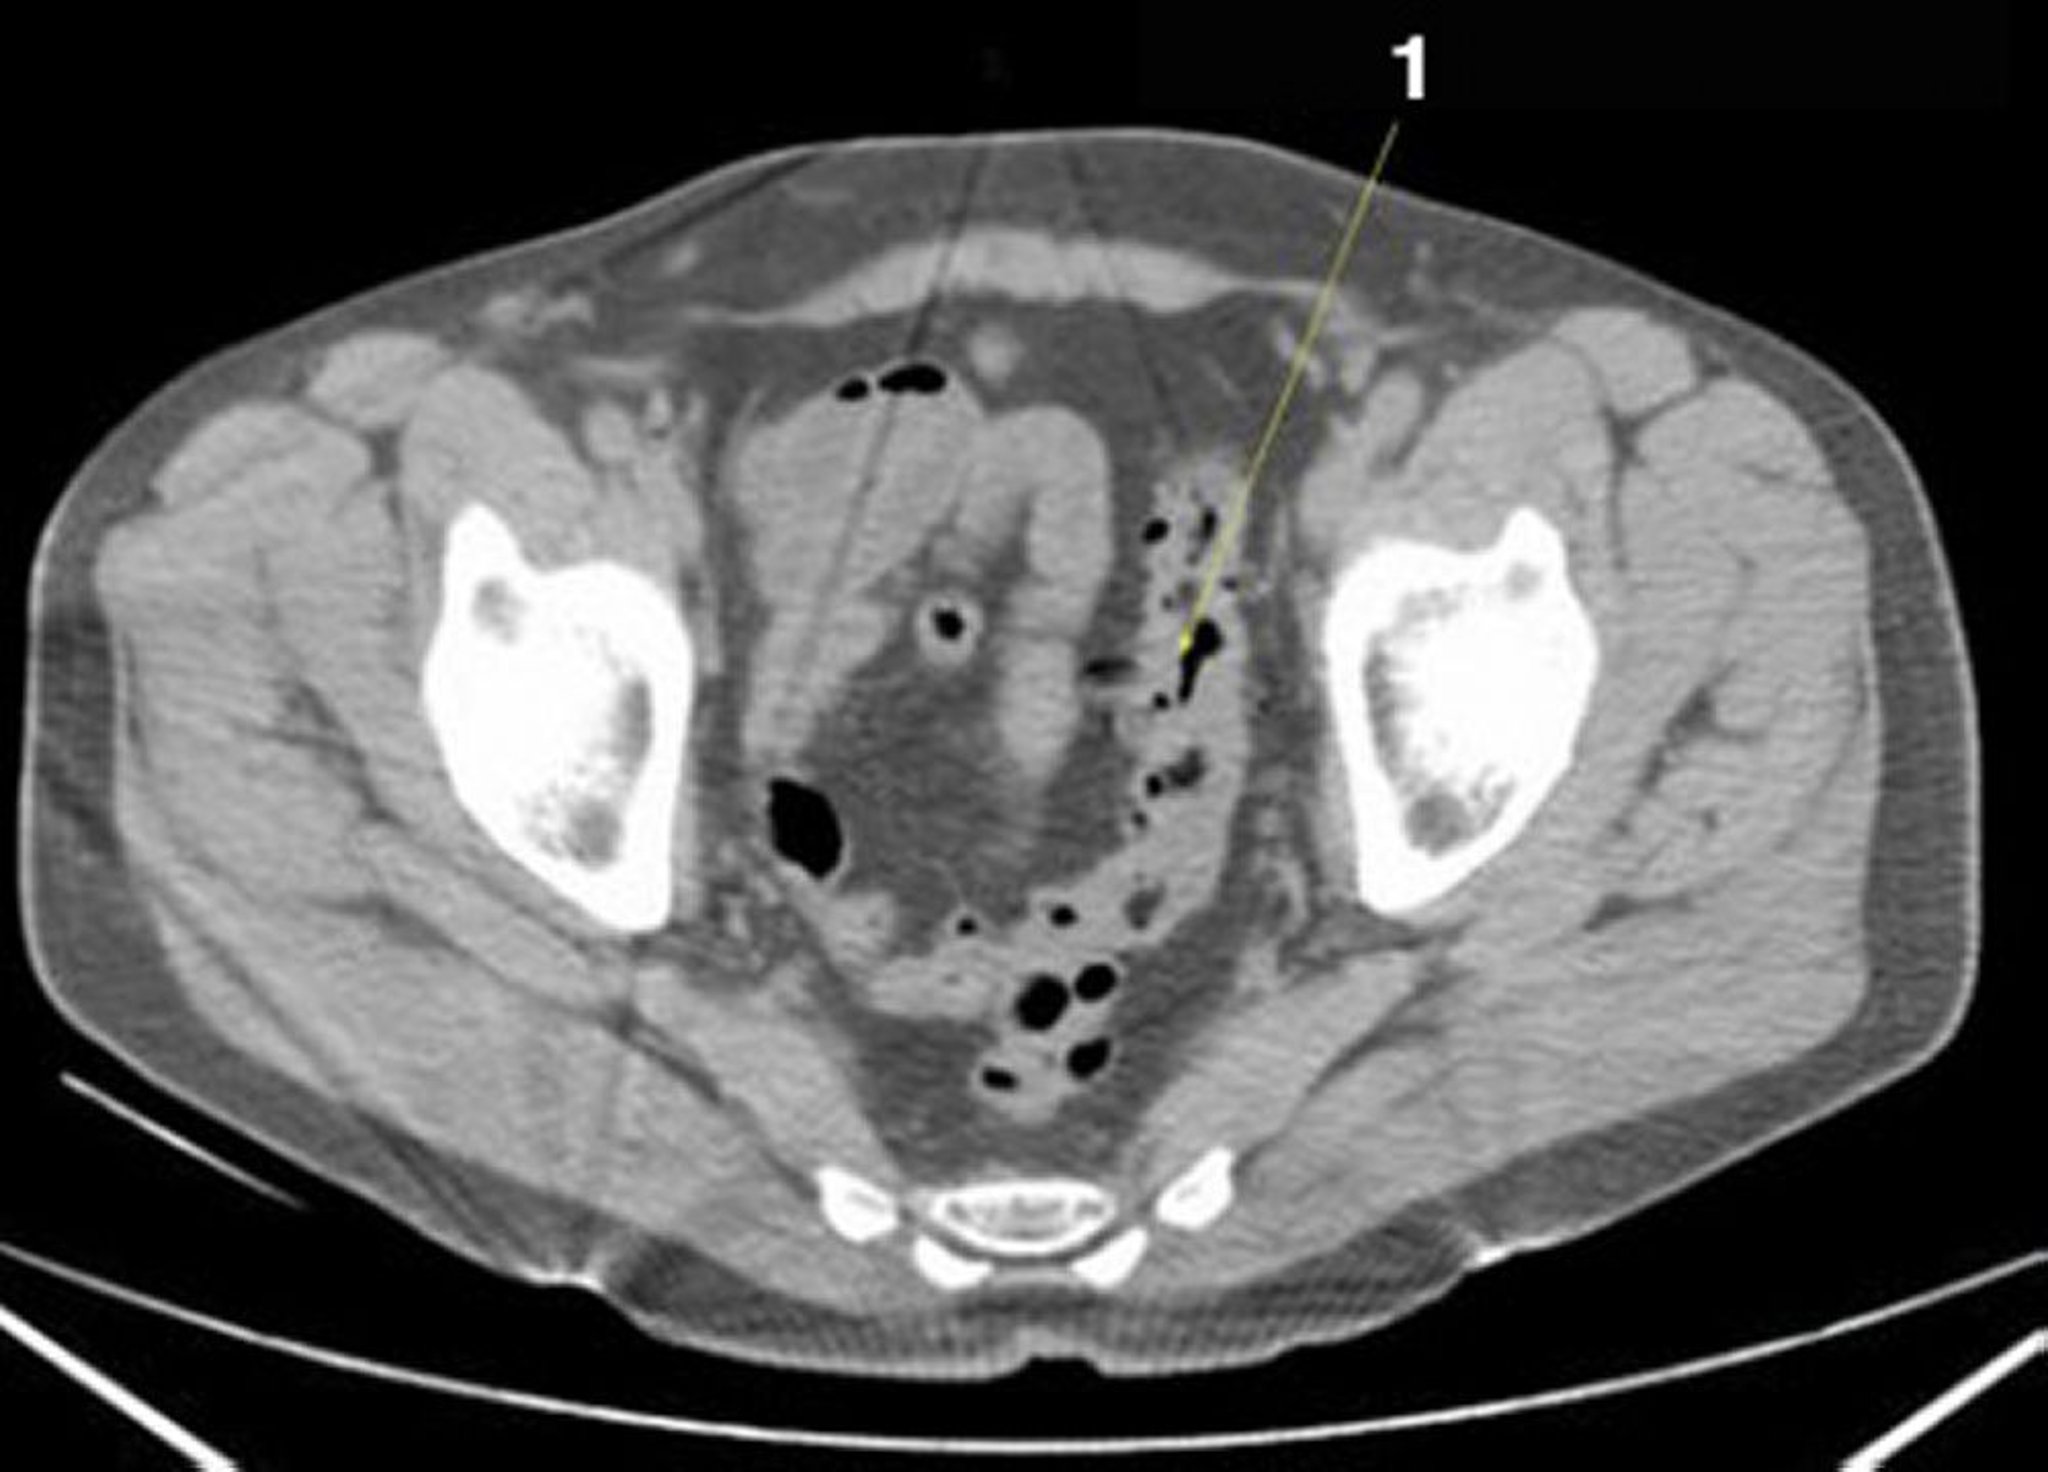

TC sem contraste do abdome e da pelve mostrando anatomia normal (lâmina 25)

1 = colo sigmoide.